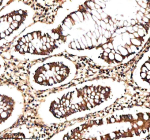

IHC analysis of NEK9 using anti-NEK9 antibody. NEK9 was detected in a paraffin-embedded section of human colon tissue. Heat mediated antigen retrieval was performed in EDTA buffer (pH 8.0, epitope retrieval solution). The tissue section was blocked with 10% goat serum. The tissue section was then incubated with 2 ug/ml rabbit anti-NEK9 antibody overnight at 4oC. Peroxidase Conjugated Goat Anti-rabbit IgG was used as secondary antibody and incubated for 30 minutes at 37oC. The tissue section was developed using an HRP secondary and DAB substrate.